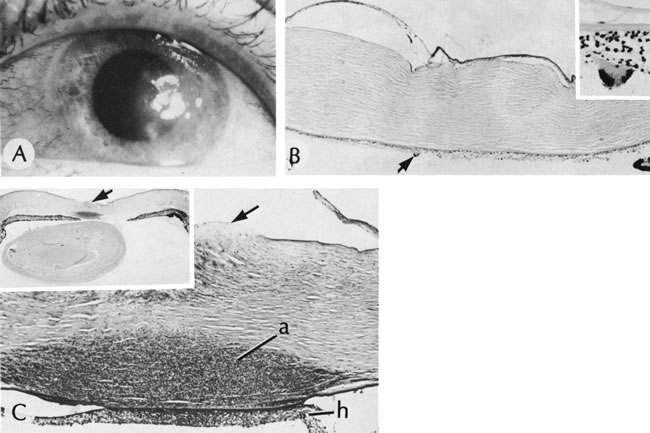

Fig. 21. Herpes simplex. A. Clinical appearance of bullous keratopathy. B. Chronic condition shows development of bullous keratopathy. The anterior chamber inflammatory reaction contains multinucleated inflammatory giant cells (arrow), shown under high magnification in inset. C. Ulcerated bullous keratopathy (arrows). A corneal abscess (a) and hypopyon (h) are present. Note (inset) the subluxation of the lens to left, caused by the loss of zonula-lens attachments on the right, resulting in a “blunted” appearance of the right side of the lens. (Courtesy of SEI Photoarchives.)